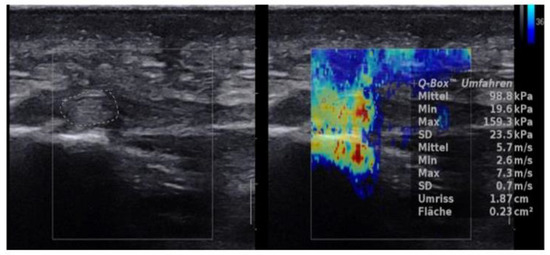

2.4.3. SWE Examination